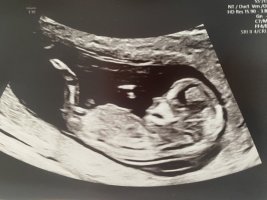

Har sett på utallige ultralydbilder til nub-tolkning, og likevel aner jeg ikke helt hva jeg skal se etter :wacky: Noen som kan tenke seg å tolke? Disse er tatt 14+4

Selv synes jeg det ser ut som jente, samtidig så så vi et tverrsnitt av baby og da var det noe langt med noe som lignet testikler mellom bena (har ikke bilde av det)

Dette er en jente. Jeg har zoomet inn på nederste bilde og man ser tydelig at det er kjønnslepper og klitoris. Pung utvikler seg ikke før i uke 15-16 så det må ha vært noe annet dere har sett.